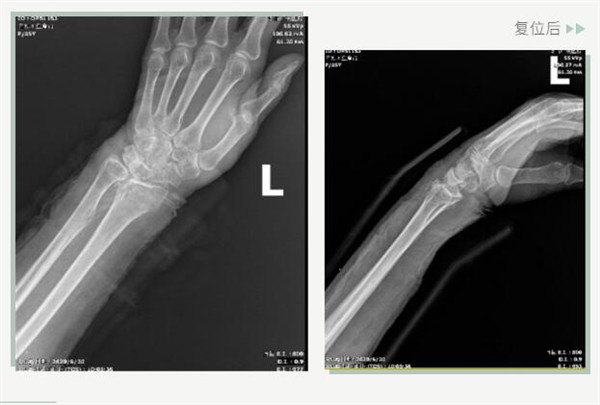

復(fù)位前

25日當(dāng)天,莊阿婆來到危立軍副院長門診,經(jīng)拍片顯示,莊阿婆左橈骨遠(yuǎn)端粉碎性骨折,左髂骨至髖臼后緣及恥骨下支骨折??紤]到莊阿婆年紀(jì)較大,基礎(chǔ)病較多,難以經(jīng)受手術(shù)創(chuàng)傷,傳統(tǒng)手法復(fù)位更為合適。推、拽、按、捺……經(jīng)過危立軍副院長一番手法復(fù)位后,再次拍片顯示莊阿婆橈骨遠(yuǎn)端骨折端復(fù)位位置良好,莊阿婆及其家人感到非常滿意。

復(fù)位后